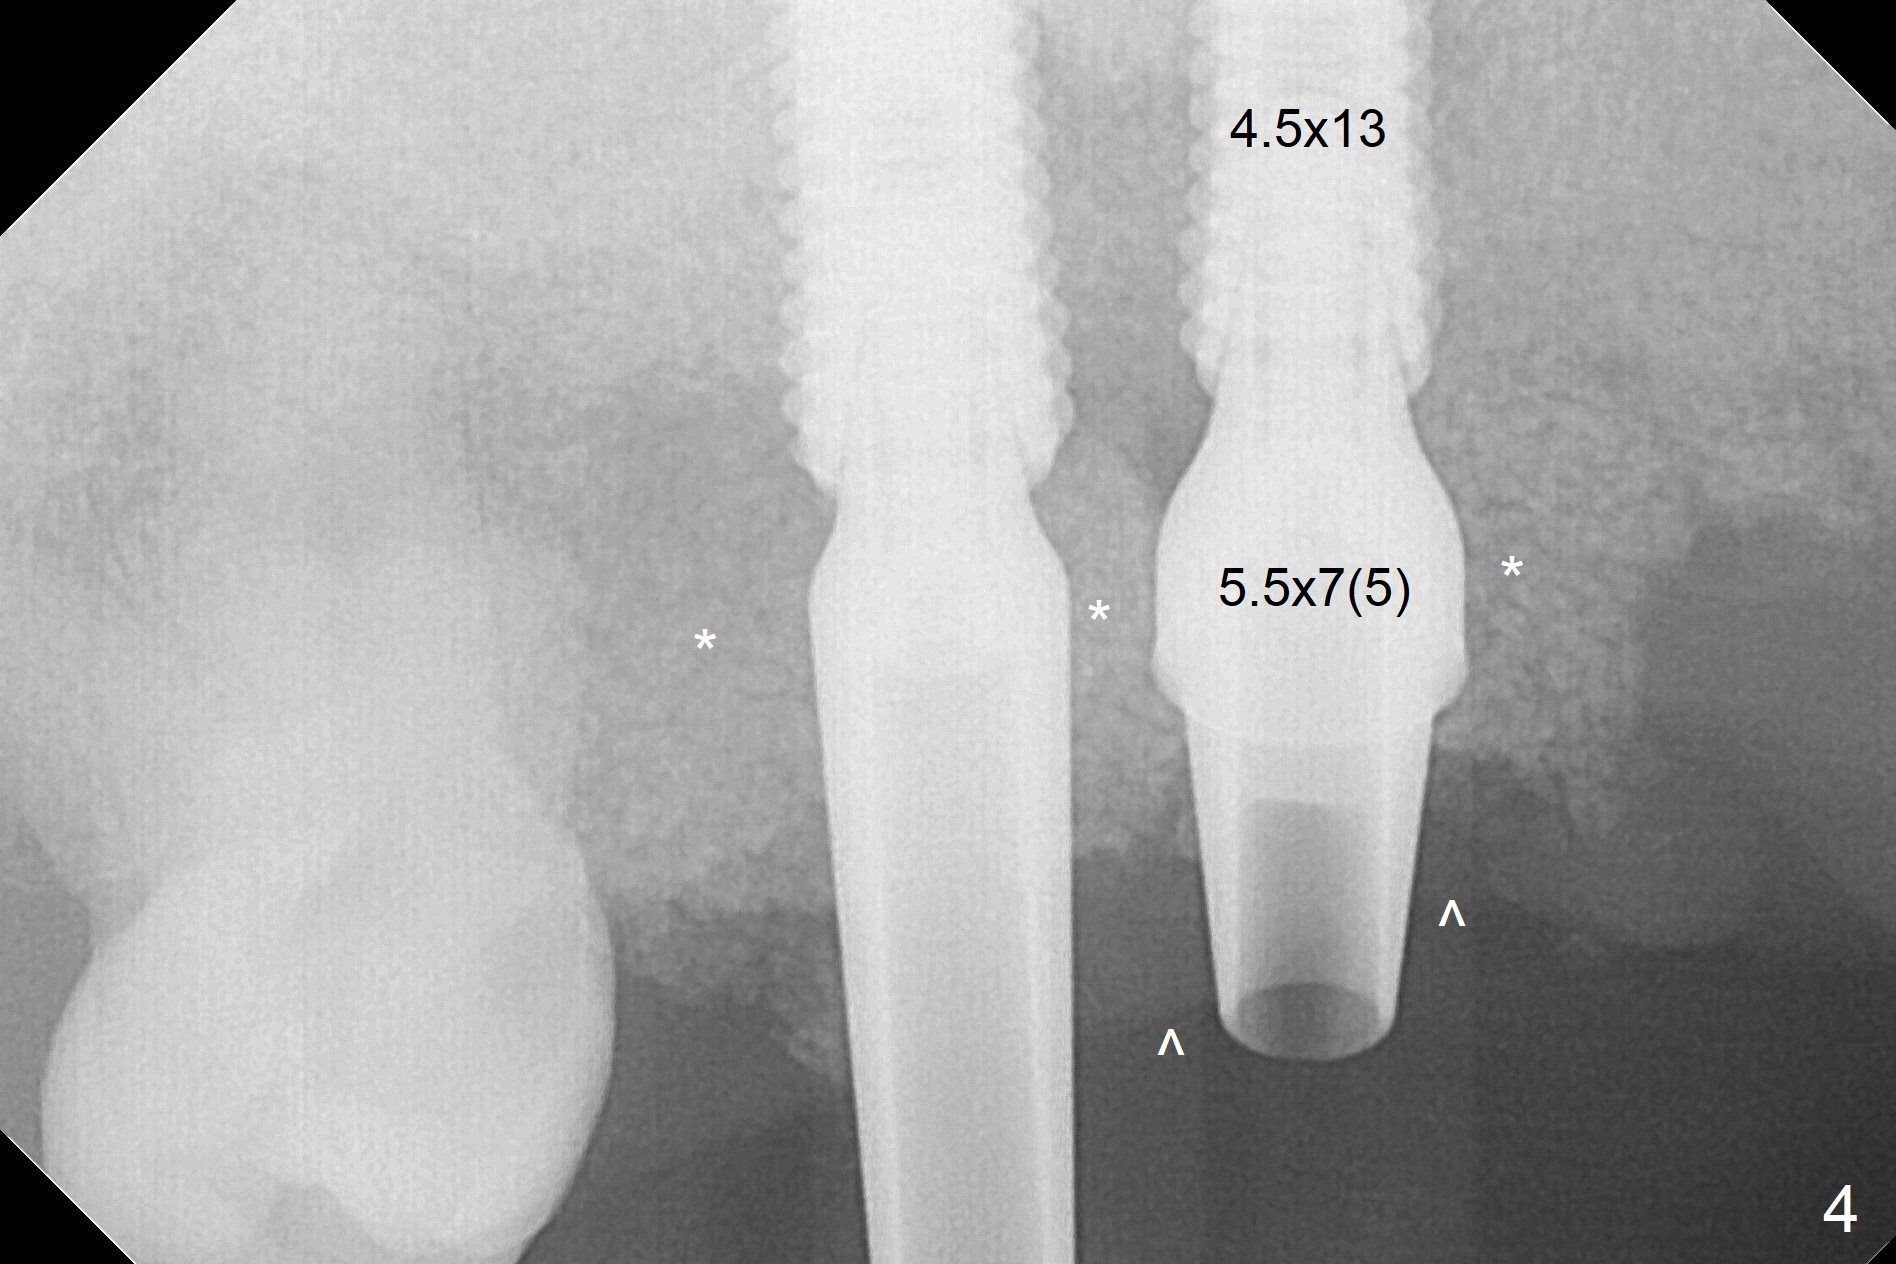

After extraction, the depths of initial osteotomy at #2, 3 and 5 are 13, 11.5 and 10 mm, respectively (Fig.1). Following adjustment of trajectory, a 3.8x13 mm UF implant is placed at #5 (Fig.2) with insertion of a 4.5x2 mm mill abutment as well as mineralized cortical/cancellous allograft (Vanilla, *). The mill abutment is chosen because the margin of a 5.5x7(5) mm cemented abutment is severely subgingival (Fig.4 at #3; ^ gingival margin). By the same token, a 4.5x3 mm mill abutment is placed at #2. In fact all of the 3 implants are placed 2-3 mm out of the bone (Fig.5). To prevent periimplantitis, abundant allograft is placed around the implants/abutments (Fig.2,4 *). Nearly 2 months postop, the mill abutment at #2 is adjusted for its height, while a 5.5x2.5 mm mill abutment is placed at #3 (Fig.6). To regain the buccal gingiva, the buccal margin of the provisional is shortened (Fig.6,7). Two weeks later, the gingival regrowth is not obvious (Fig.8 (nearly 3 months postop)). Local poor oral hygiene remains. A provisional FPD is fabricated. If his occlusion is normal for another 2 weeks, impression will be taken for upper (or UL) permanent restoration.